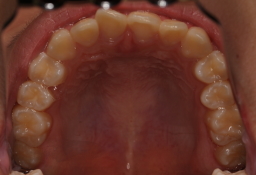

上顎の歯 歯磨きはあんまりしないので、軽度の歯周炎が ありますが、 フッ素塗布とフッ素飲料とシーラントでむし歯ゼロです。 2015年04月現在 |